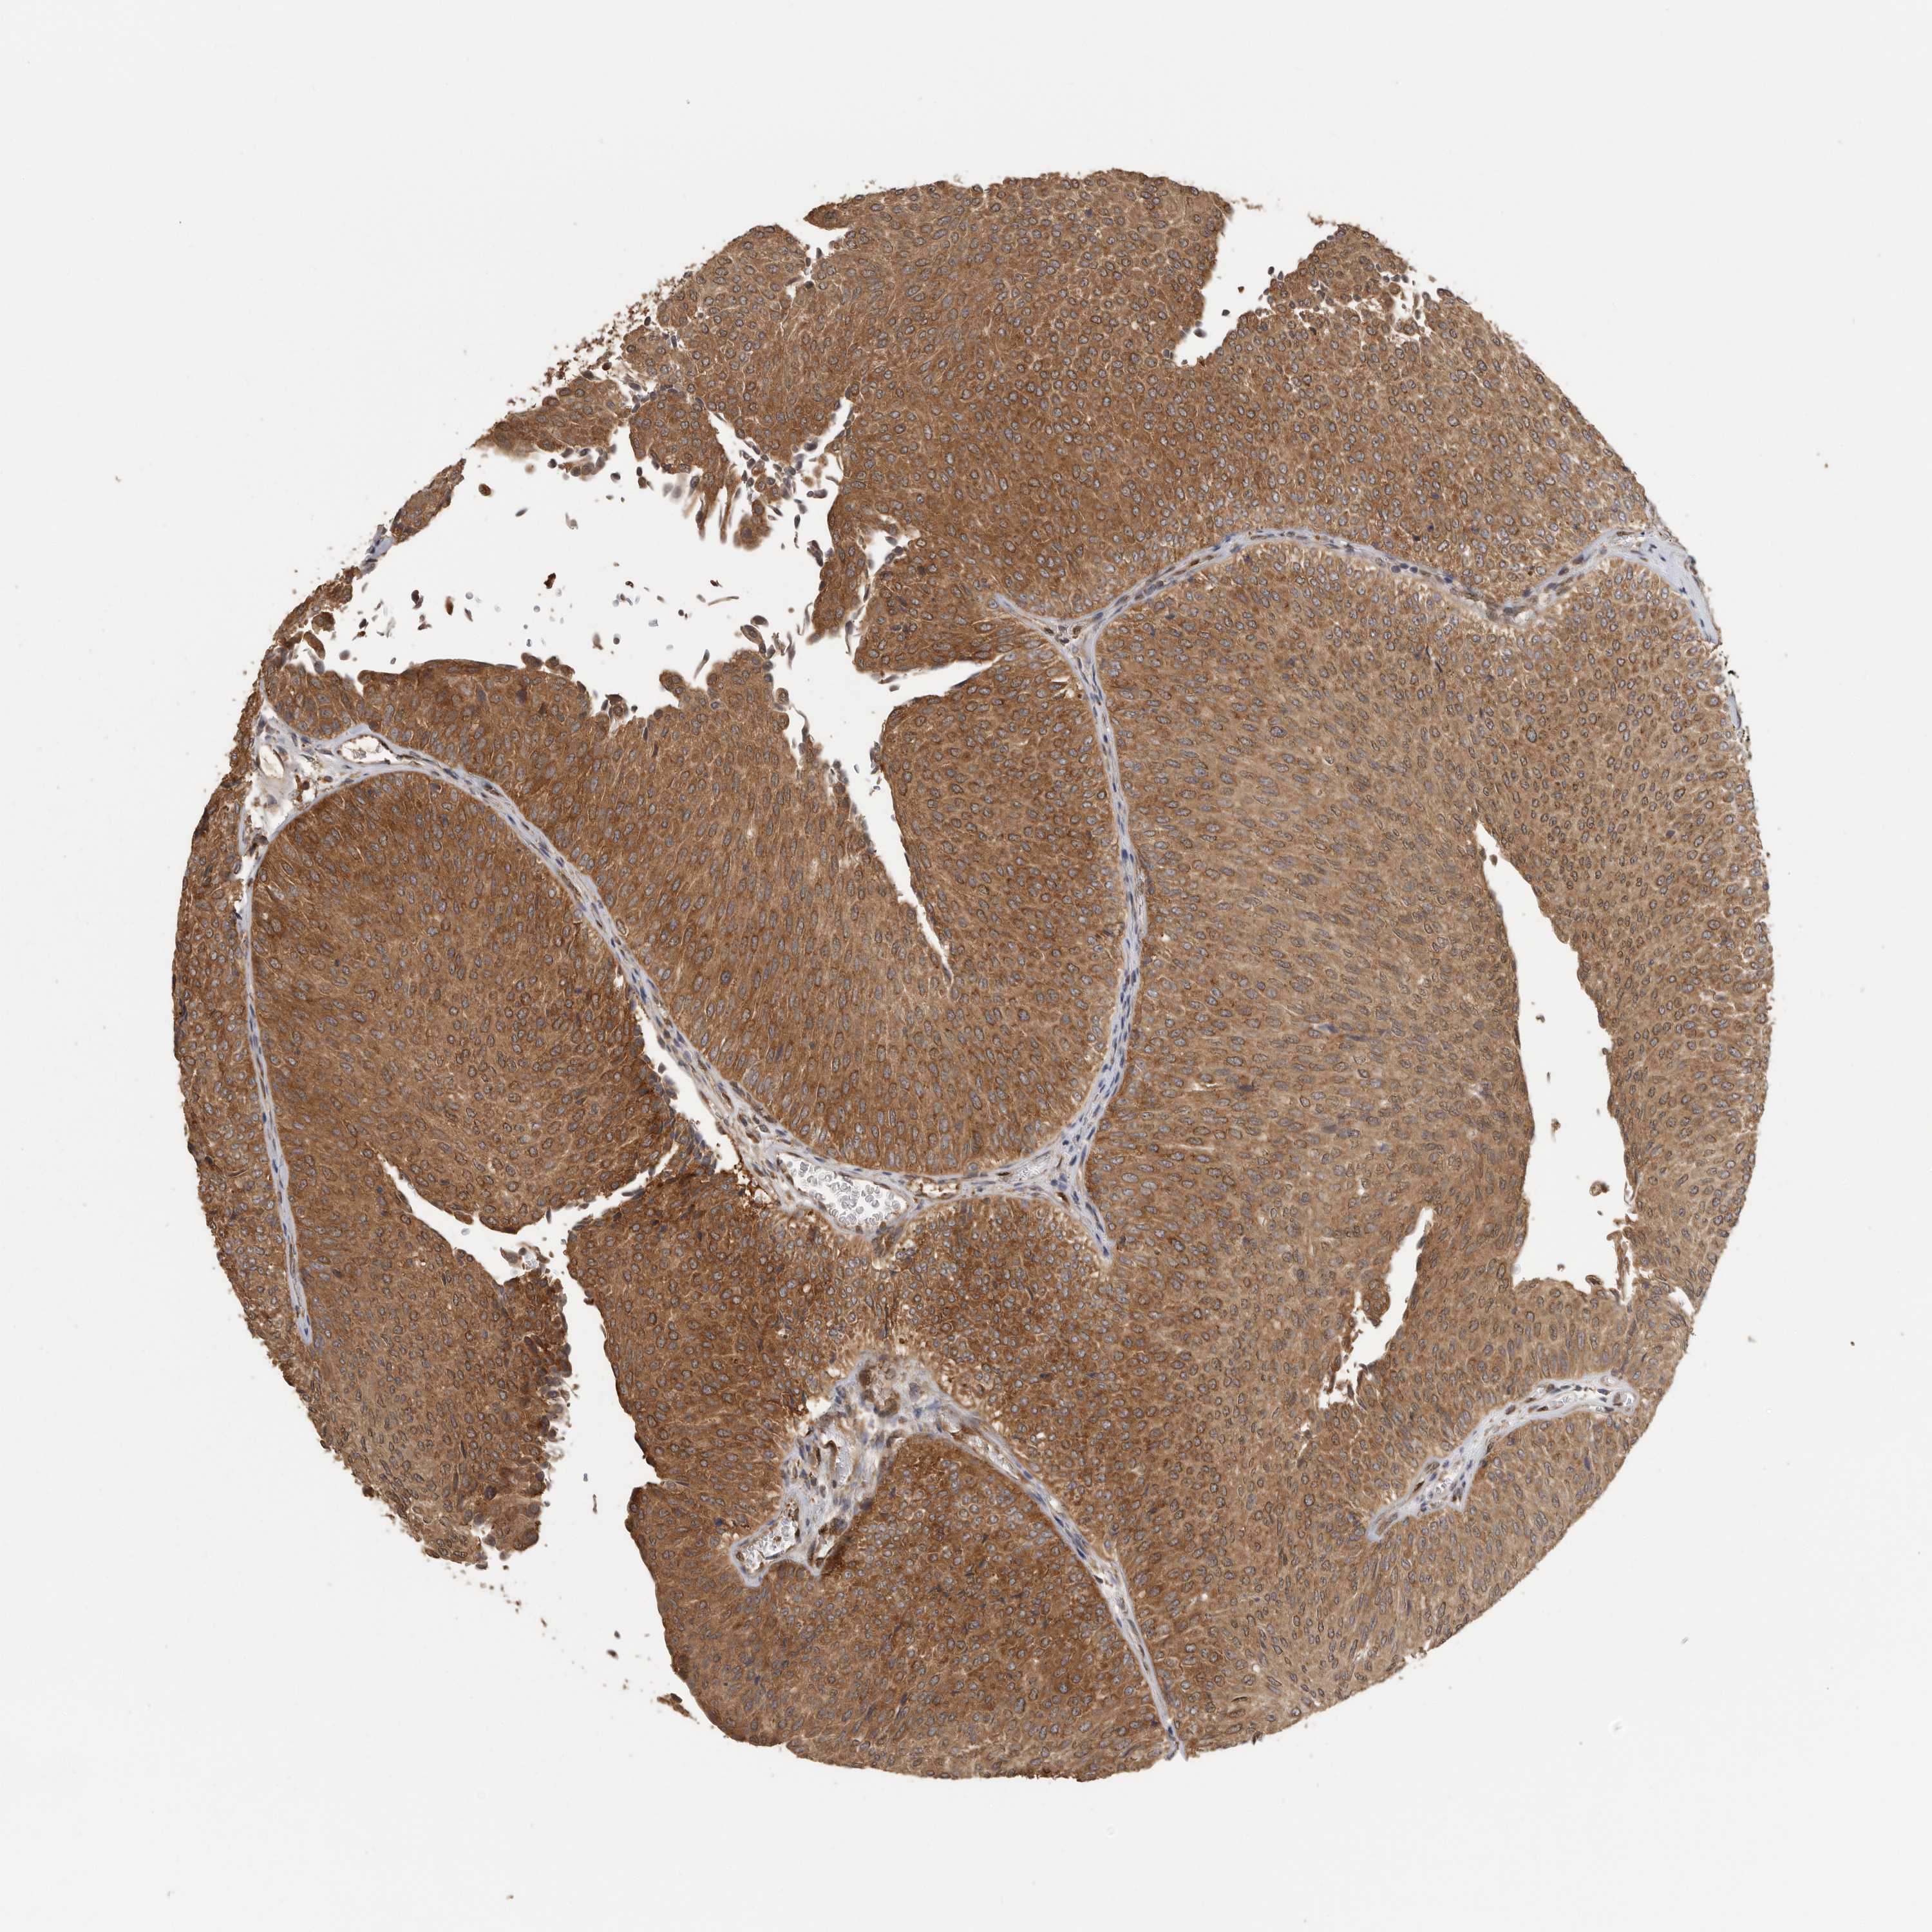

UROTHELIAL CANCER - Protein expressioni

A mouse-over function shows sample information and annotation data. Click on an image to view it in a full screen mode. Samples can be filtered based on level of antibody staining by selecting one or several of the following categories: high, medium, low and not detected. The assay and annotation is described here.

Note that samples used for immunohistochemistry by the Human Protein Atlas do not correspond to samples in the TCGA dataset.

Antibody stainingi

Antibody staining in the annotated cell types in the current human tissue is reported as not detected, low, medium, or high, based on conventional immunohistochemistry profiling in selected tissues. This score is based on the combination of the staining intensity and fraction of stained cells.

Each image is clickable and will lead to virtual microscopy that enables deeper exploration of all samples and also displays staining intensity scores, fraction scores and subcellular localization as well as patient and tissue information for each sample.

Antibody HPA018520

Antibody HPA021051

Antibody HPA029426

Urothelial carcinoma, Low grade

Urothelial carcinoma, High grade